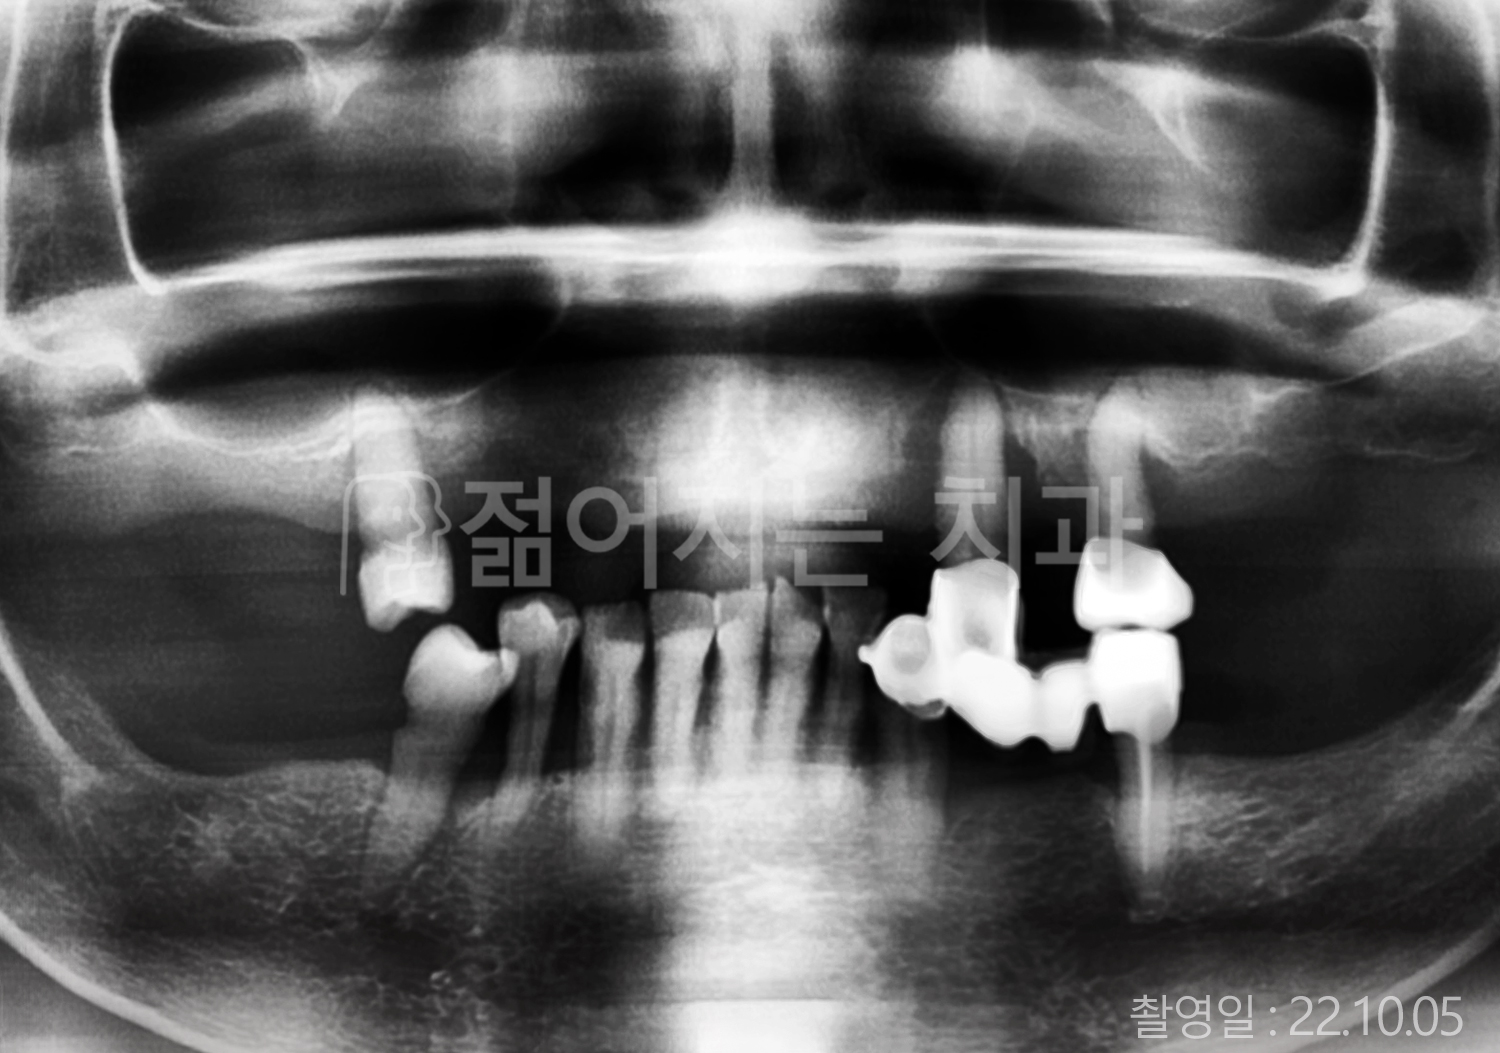

• 50대 고혈압, 당뇨, 고지혈증 전체치아 10개 이상 임플란트

• 50대 고혈압, 당뇨 전체치아 10개 이상 임플란트